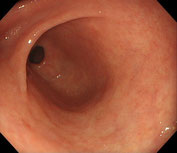

大腸(正常) |

大腸憩室 |

大腸ポリープ |